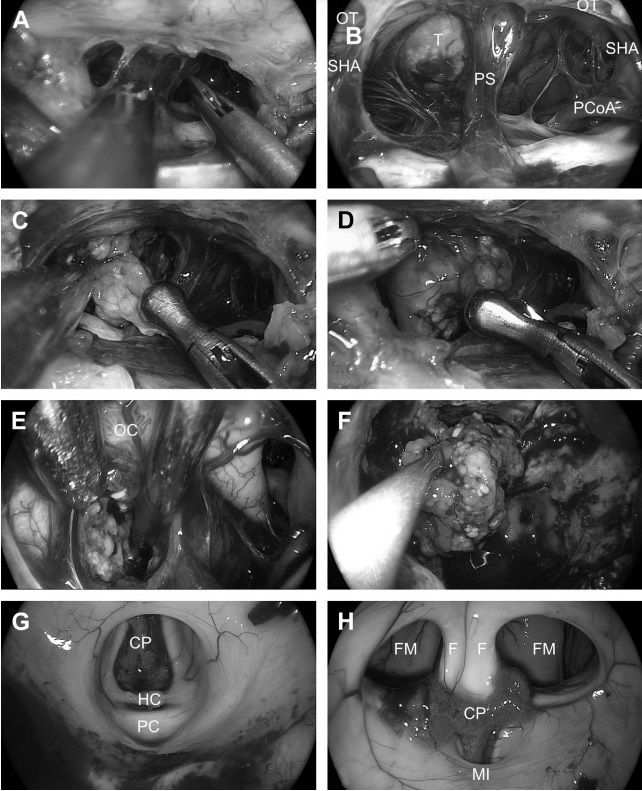

![图16为硬膜内操作阶段。(A)锐性分离蛛网膜。(B)暴露鞍膈上区。可见垂体柄(PS)、后交通动脉(PCoA)、垂体上动脉(SHA)、视神经(OT)和肿瘤(T)。(C)切除肿瘤。双手用抓钳和解剖钳进行囊外剥离。垂体柄向左侧偏。(E)切换到30°内窥镜顺利实现交叉后肿瘤去体积(视交叉[OC])(F)将一大块肿瘤从三脑室移至蝶骨腔。(G)完全切除肿瘤后然后检查三脑室背侧部分(脉络膜丛[CP],缰连合[HC],后连合[PC])。(H)使用45°内窥镜检查三脑室前部(脉络丛(CP),穹窿[F],门室孔(FM)和丘脑间粘合(MI))。](https://www.incsg.cn/uploads/allimg/240130/1-2401301014203H.jpg)

图16为硬膜内操作阶段。(A)锐性分离蛛网膜。(B)暴露鞍膈上区。可见垂体柄(PS)、后交通动脉(PCoA)、垂体上动脉(SHA)、视神经(OT)和肿瘤(T)。(C)切除肿瘤。双手用抓钳和解剖钳进行囊外剥离。垂体柄向左侧偏。(E)切换到30°内窥镜顺利实现交叉后肿瘤去体积(视交叉[OC])(F)将一大块肿瘤从三脑室移至蝶骨腔。(G)完全切除肿瘤后然后检查三脑室背侧部分(脉络膜丛[CP],缰连合[HC],后连合[PC])。(H)使用45°内窥镜检查三脑室前部(脉络丛(CP),穹窿[F],门室孔(FM)和丘脑间粘合(MI))。